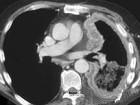

问题 男,68岁,胸痛,呼吸困难,咳嗽1个月余,请结合影像学检查,选出最可能的诊断 ( )

选项 A.间皮瘤 B.肺癌 C.肺转移瘤 D.淋巴瘤 E.肺结核

答案 A